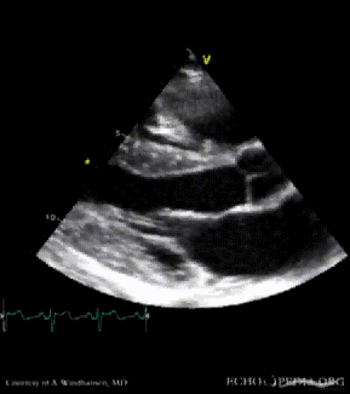

Severe Hypertrophic Cardiomyopathy (HCM)

Case description: Severe Hypertrophic Cardiomyopathy (HCM)

Courtesy of: A. Windhausen, AMC, The Netherlands

MM0003.gif MM0010.gif